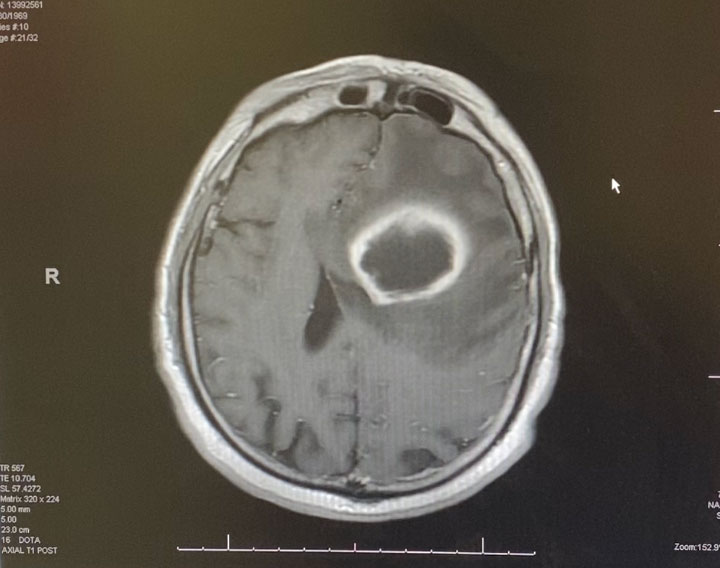

Because the lesion was sizeable, and causing much mass effect, and the diagnosis was unclear, and the patient was young with no other existing disease, it was decided to emergently bring the patient to the operating room for surgical removal of the mass. Surgery was performed by Dr. Michael Brisman. Stereotactic Brainlab navigation was utilized. A small left frontal craniotomy was performed. After making a small cortical incision, the Vycor transparent tubular retractor was inserted into the lesion. Thick yellow liquid was encountered under pressure consistent with frank purulence. (Image 2 shows intra-operative image of Vycor tubular retractor in deep left frontal mass with thick purulent material coming out under pressure.) Cultures were sent. The pus was fully washed out with gentle antibiotic irrigation.

Image 2: Intra-operative image of Vycor tubular retractor in deep left frontal mass with thick purulent material coming out under pressure.